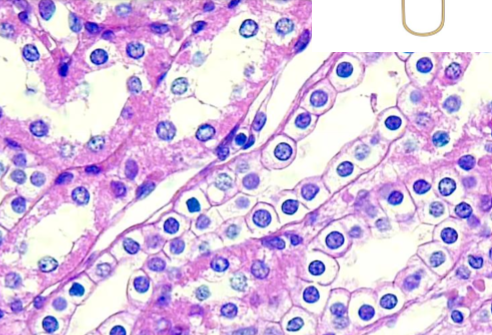

What is this?

simple cubodial

what is simple cubodial epithelial?

single layer of cells, as tall as wide

nucle in middle

absorption and secretion

kidney tubules, endocrdine glands